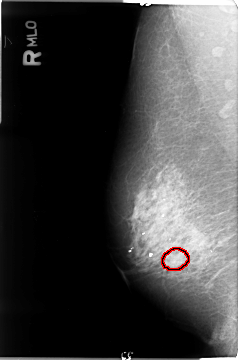

B_3043_1.RIGHT_MLO

FILE: B_3043_1.RIGHT_MLO.OVERLAY

TOTAL_ABNORMALITIES 1

ABNORMALITY 1

LESION_TYPE MASS SHAPE OVAL MARGINS CIRCUMSCRIBED-OBSCURED

ASSESSMENT 3

SUBTLETY 3

PATHOLOGY UNPROVEN

TOTAL_OUTLINES 1

BOUNDARY